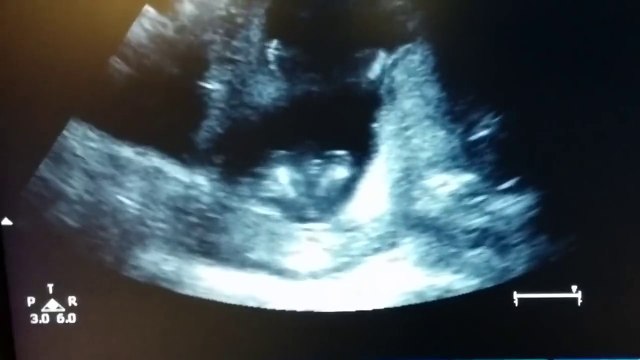

Baby Yawns in Womb - 4D Ultrasound Video Footage